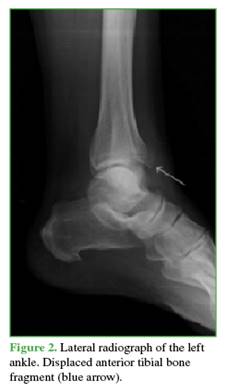

A 62-year-old housewife, previously independent in her self-care and household activities, with non-insulin-dependent type 2 diabetes mellitus, controlled arterial hypertension, and asymptomatic bilateral hallux valgus, presented to the Emergency Department of our institution after suffering an inversion trauma while descending a step. She reported pain, edema, and an inability to stand or walk. On examination, she had pain on palpation of the dorsum of the foot, spontaneous toe movement, and a symmetrical palpable foot pulse. No deformities or open injuries were observed. She underwent anteroposterior and lateral radiographs of the right ankle, which revealed asymmetry at the tibiofibular junction and loss of tibial joint congruity (Figures 1 and 2).

Based on these findings, a CT scan was requested, revealing a displaced anterolateral Tillaux-Chaput tubercle fracture, rotated in a shear pattern, and a simultaneous displaced Volkmann’s posterior malleolus fracture. These fractures were classified as Rammelt type III and Bartoníček type II, respectively (Figure 3).